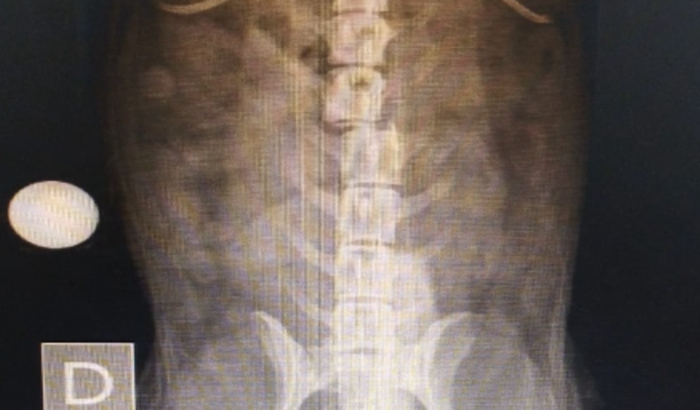

Ola meu nome é Aline… e criei essa vaquinha online. Pra ajudar nosso cãozinho da raça poodle Nosso Menino BILI que foi atropelado por uma moto. Que não prestou socorro. Ele teve sua coluna fraturada e pata quebrada. Está precisando. Urgente de cirurgia. Vamos juntos somos mais fortes.